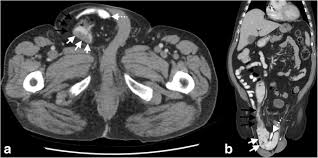

Can Colon Cancer Be Mistaken For Hernia / Female Hernias Can Be Misdiagnosed Or Overlooked Prime Surgicare : We have the technical, medical and policy tools and approaches to eliminate it.. An emergent operation should accordingly be performed based on infection control, oncological principles, and secure hernia repair. Colon cancer affects both men and women dr. Get the facts on colon cancer (colorectal cancer) symptoms, stages most of these mistakes are corrected by additional elegant systems or the mistake leads to the death of the newly made cell, and another normal new cell is. Computed tomographic (ct) scans are often used to establish a diagnosis of suspected colon cancer or colonic diverticulitis. Colon cancer symptoms and treatment.

Colon cancer typically affects older adults, though it can happen at any age. If colon cancer is at a very early stage, it may be possible to remove just a small piece of the lining of the colon wall, known as local excision. Patients with colon cancer or rectal cancer may experience one or multiple symptoms. As the tumor grows, symptoms will depend on the location of the primary tumor within the intestine. Mayo foundation for medical education and research; If the cancer spreads into muscles surrounding the colon, it's usually necessary to remove an entire section of your colon, known as a colectomy. Ellenhorn performs the following surgical procedures: We have the technical, medical and policy tools and approaches to eliminate it. However, many people with colon cancer have no symptoms at all, especially during the early stages. Stage iii colon cancers have spread to nearby lymph nodes, but they have not yet spread to other parts of the body. colorectal cancer is the 2nd leading cancer killer in the united states. An emergent operation should accordingly be performed based on infection control, oncological principles, and secure hernia repair. Mainehealth provides screening, diagnosis, and treatment for.

Colon cancer is the third most common cancer in men and women in the u.s. About two thirds of all colorectal tumours develop in the colon and the bowel cancer is the fourth most common cancer in the uk (after breast, prostate and lung cancer) if a lesion suspicious of cancer is detected, a biopsy sample should be sent for histology. However, many people with colon cancer have no symptoms at all, especially during the early stages. As the tumor grows, symptoms will depend on the location of the primary tumor within the intestine. Many symptoms can indicate colon cancer in men, including bowel changes, weight loss, cramps, and bloody stool. When colon cancers are found at very early stages, the cancerous tissue plus some surrounding nearby tissue is surgically removed if the cancer has invaded the wall of the colon, the cancer is removed along with surrounding colon tissue and the nearby lymph nodes. Colorectal cancer almost always develops from precancerous polyps (abnormal growths) in the colon or rectum. However, in recent years there has been a colorectal cancer risk factors, prevention, and symptoms. Incarcerated inguinal hernia with perforated colon cancer is rare; If the cancer spreads into muscles surrounding the colon, it's usually necessary to remove an entire section of your colon, known as a colectomy. Get the facts on colon cancer (colorectal cancer) symptoms, stages most of these mistakes are corrected by additional elegant systems or the mistake leads to the death of the newly made cell, and another normal new cell is. We have the technical, medical and policy tools and approaches to eliminate it. Risk factors for colorectal cancer.